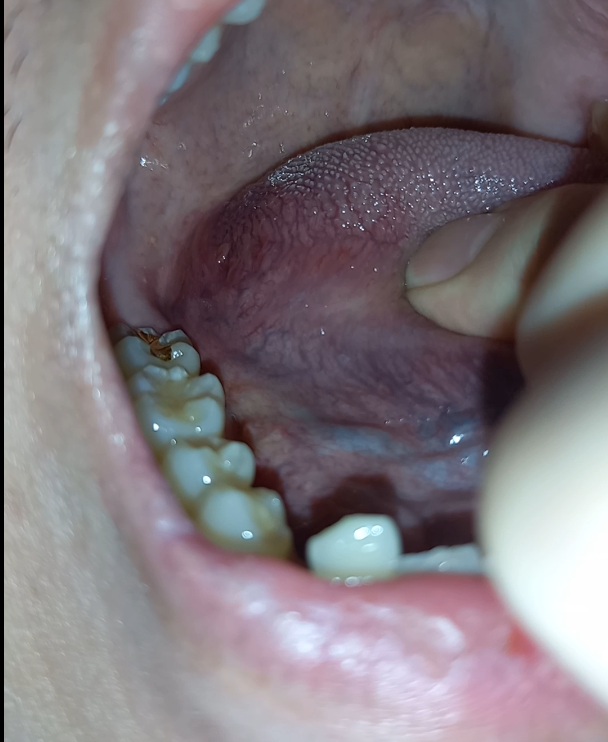

혀 측면 가장 끝쪽에 돌기같은게 나있는걸 발견하게 됐습니다.

혹시나 해서 반대편도 확인해보니 비슷한 돌기가 있더군요.

왼쪽 오른쪽 사진은 첨부해 두겠습니다.

돌기 위에 빨간 부위는 실핏줄같은것처럼 생겼습니다. 혀를 앞으로 당겨오니 보이더라구요. 이것도 양쪽 다 보입니다.

양쪽에 보이는 돌기는 정상적인 구조물인건가요? 아님 치료가 필요한 건가요?

• 1번 째 사진